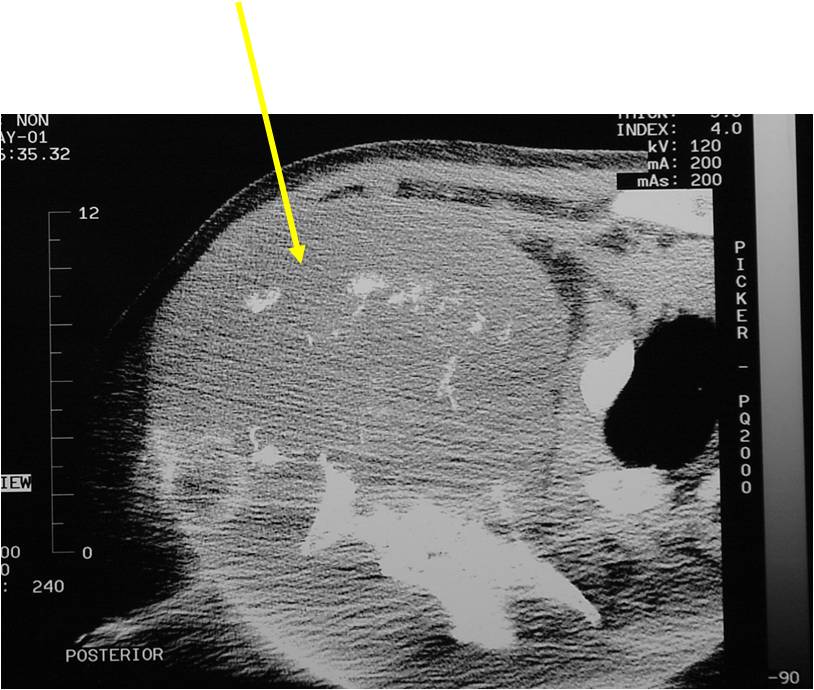

Radiology emulates pathology: Biphasic Tumor

- One region low grade chondrosarcoma

- Second more aggressive area with bone destruction, lysis of calcification, soft tissue mass

- Cortical permeation and a soft tissue mass in 70% of cases

Ill-defined, lytic intraosseous lesion

- Or extraosseous soft tissue mass

- Devoid of calcifications in continuity with lesions having the features of a cartilaginous tumor

Characteristically abrupt transition between chondroid tumor and dedifferentiated, lytic component

(Right Arrow)Aggressive Lytic Area (Dedifferentiated Sarcomatous Component) Cortical Destruction Soft Tissue Mass without Calcification